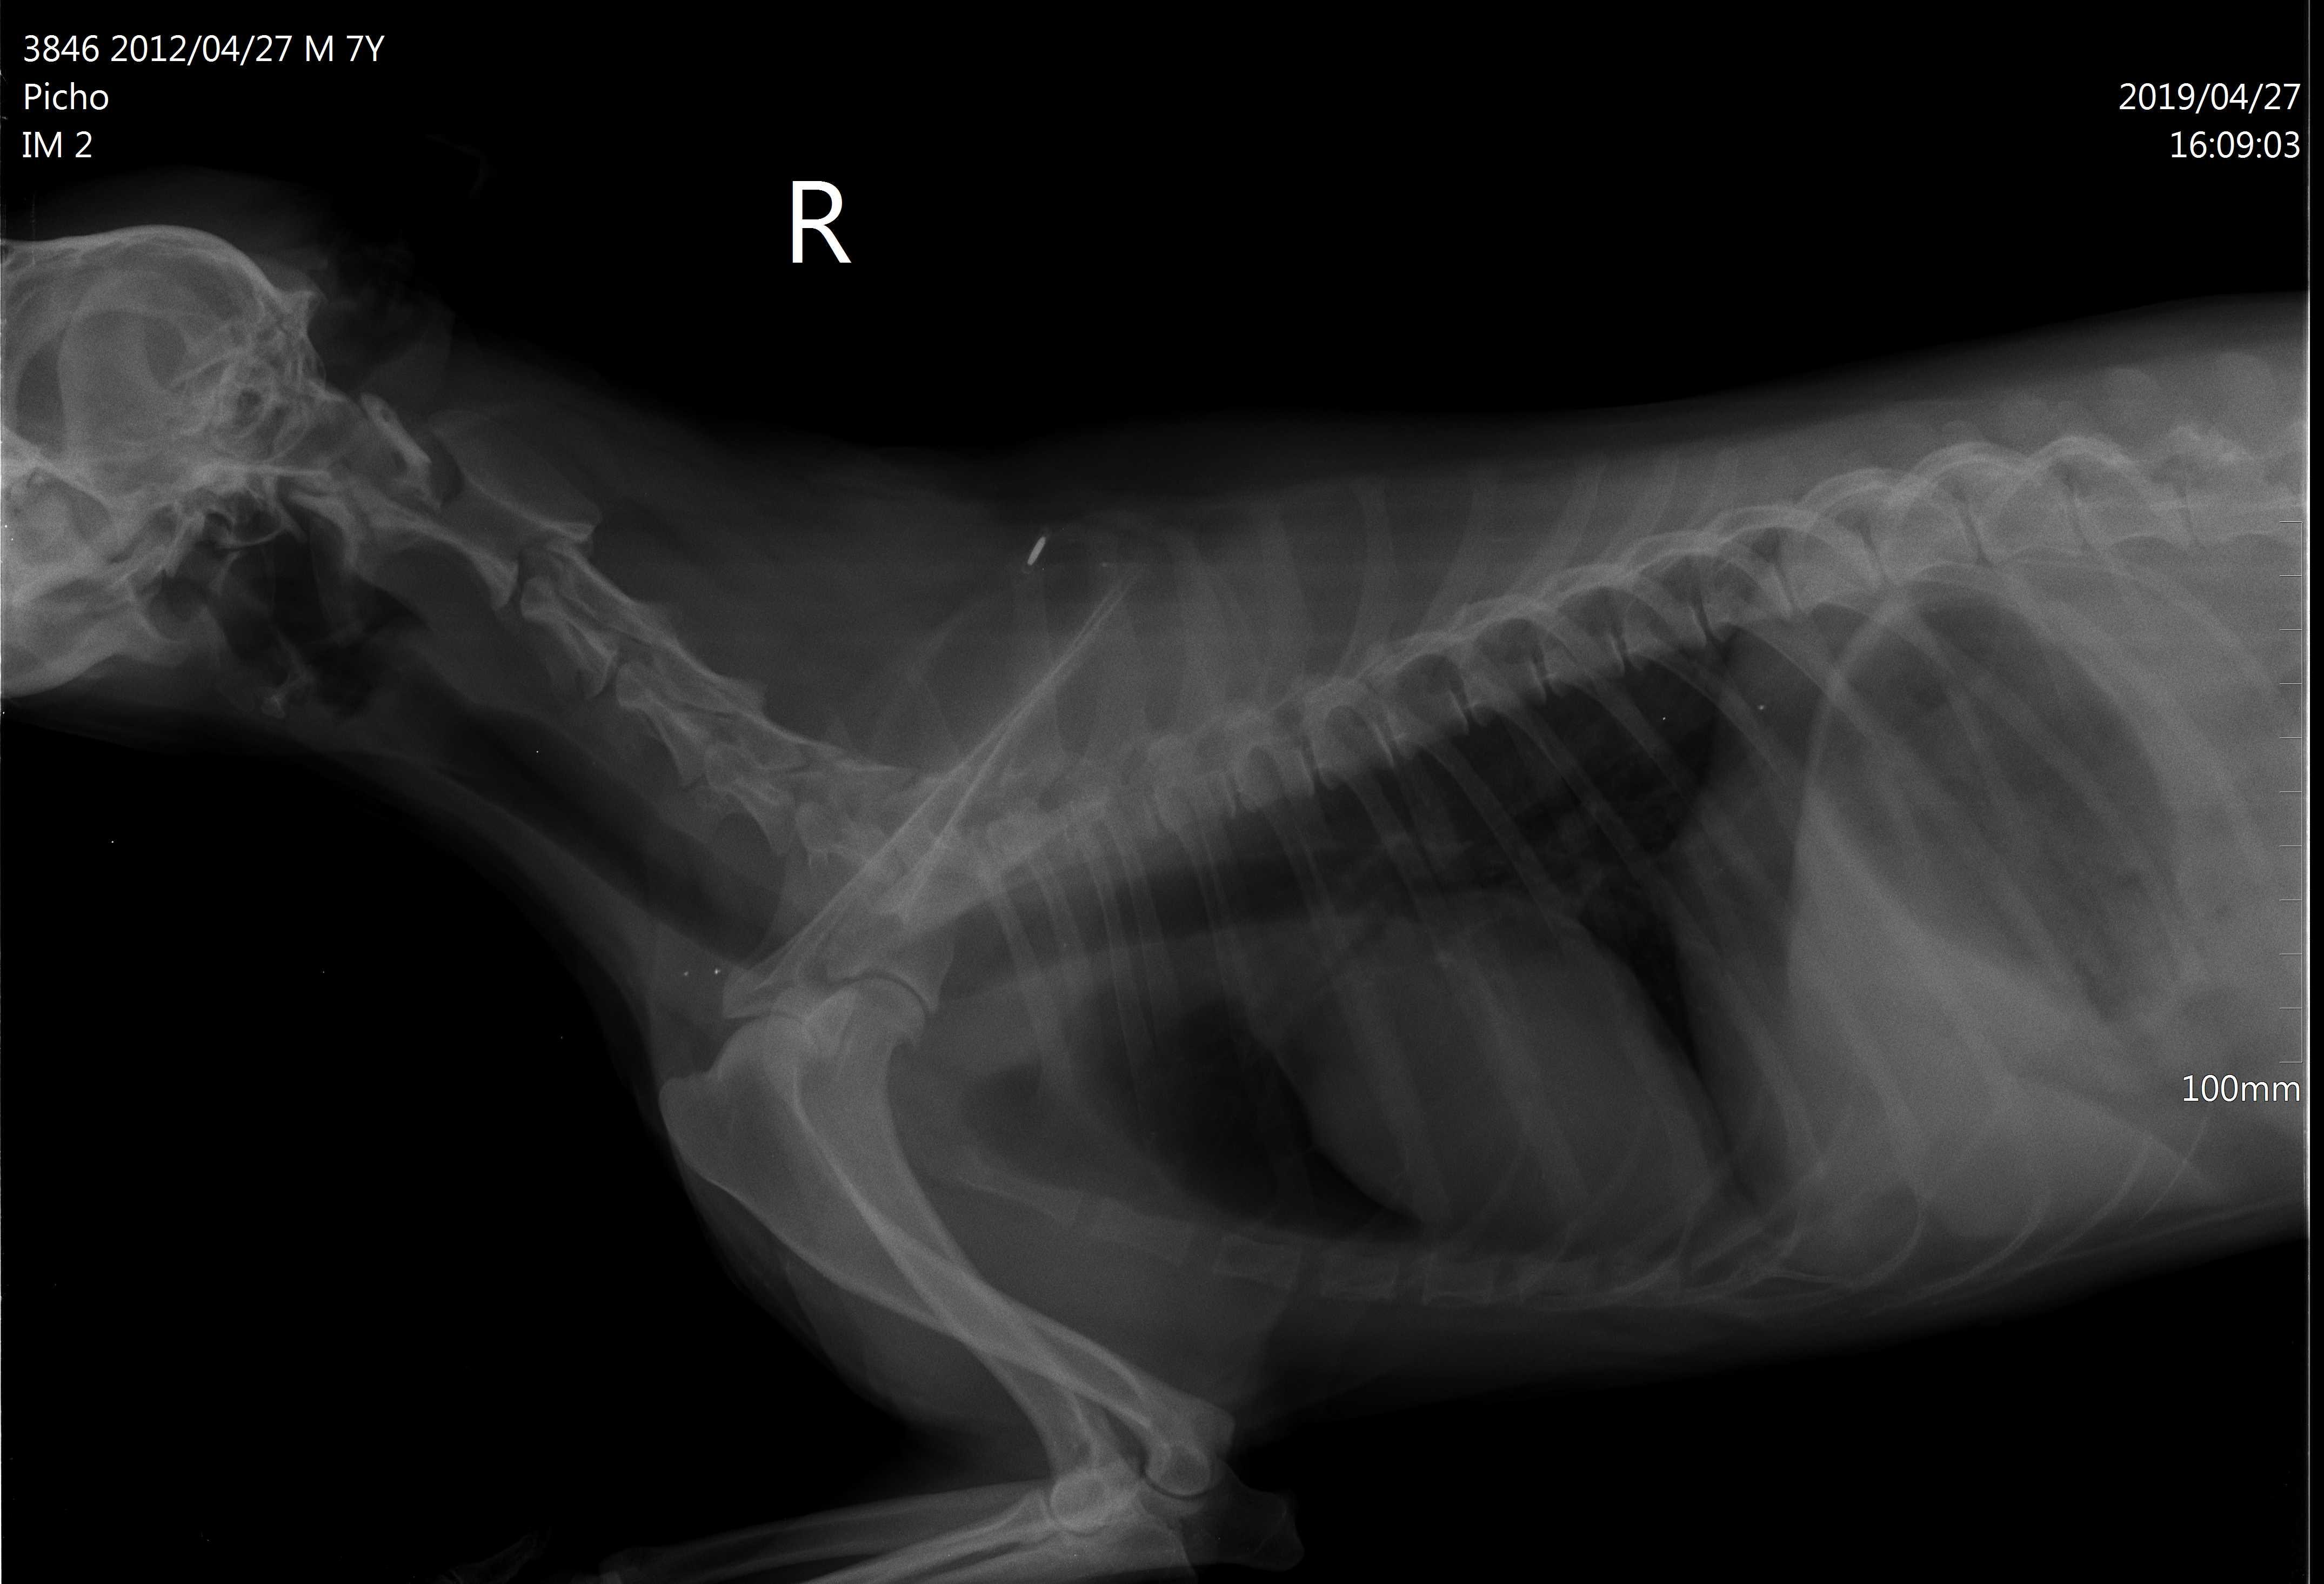

Dears, My dog had a seizure 1 month ago, 2 days ago he was vomiting. Then he was playing with my daughter and she accidentally hit him somewhere in the neck as she says, in the morning we found him paralysed with all legs he can't walk. We had an X-ray, attached see pics, our vet says he has a fluid between neck and spine that causes brain compression and he needs surgery. Please advise, my daughter is nervous she thinks that it is because of her, could this be the reason?

I hardly think your daughter could have hit Pich hard enough to cause this. It is more likely that this condition was underlying already especially with the history of a seizure. The x-rays are difficult to assess on this forum - when we try to enlarge them they get very grainy so I cannot comment on that part. Hope this helps. Best wishes.

I remember this question from before. There is no way your daughter hit this dog hard enough to cause paralysis unless she ran him over in a car or hit him with a baseball bat. Regardless, of whether she did or didn't cause it Pich needs surgery. I see the fluid your vet has noted. Your only options are to do the surgery or humane euthanasia - you cannot let him suffer like this. This has already been going on for weeks. Please do the surgery or relieve his suffering. I'm sorry you are going through this but you need to do what is best for Pich.